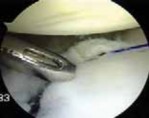

Anchor Placement and Capsulolabral Plication

With the glenoid prepared and the tissue mobilized, fixation begins at the most inferior aspect of the lesion, typically at the 5:30 or 6 o'clock position. Modern fixation relies on either biocomposite or all-suture anchors, typically 1.5 mm to 2.9 mm in diameter. The drill guide is introduced through the anteroinferior portal, and the anchor is deployed on the articular margin (1-2 mm onto the articular cartilage face) to recreate the anatomical labral bumper. The trajectory of the drill is paramount; it must be directed slightly medially to avoid penetrating the articular surface of the glenoid vault.